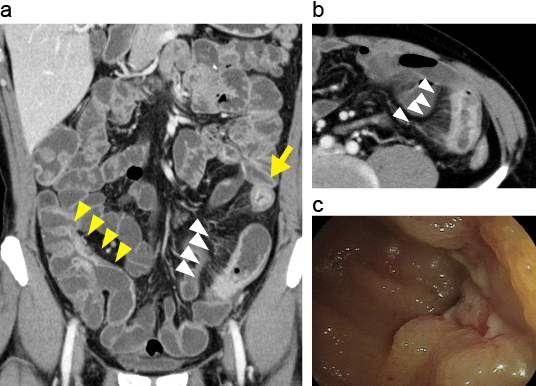

CTエンテログラフィーによる小腸病変

小腸・大腸型クローン病。

A. CT enterography(CTE)冠状断像。

B. CTE横断像。回腸末端部~上行結腸にかけて縦走潰瘍が形成され、同部位は腸管壁は強く造影され、直線化と層状化が認められる(黄矢頭)。さらに、口側の回腸に強い炎症部位では腸間膜直細動脈の拡張像(comb sign、白矢頭)とtarget sign(黄矢印)を認める。

C. 回腸末端部内視鏡像。縦走潰瘍を認める。

出典

img

1: 難治性炎症性腸管障害に関する調査研究(久松班):一目でわかるIBD 炎症性腸疾患を診察されている先生方へ(第四版) 「令和4年度において、厚生労働科学研究費補助(難治性疾患等政策研究事業(難治性疾患政策研究事業)を受け、実施した研究の成果」、2023年、P29